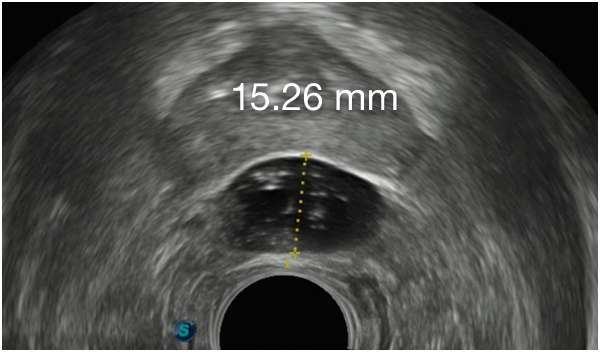

Barrigelの初回留置-連続症例(同日内)

TRUS画像提供:Daniel R. Welchons, MD

Urologist; New York, United States

DR. WELCHONSの留置テクニック